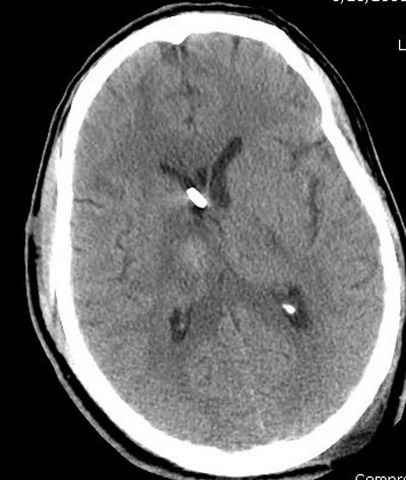

больному 42, автоавария, политравма, открытая черепномозговая травма, безсознании, открытый перелом бедра, размозжение мягких тканей, дефект кожи на передней поверхности бедра около 13 см2 от ожога, компартмент синдром.

Наблюдается службой травмы и нейрохирургии (ICP) Increased Intracranial Pressure by ventricular cateter

монииторинг